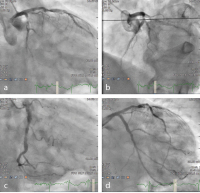

Angiographie

Abbildung 4a-d: (a-c) Diagnostische Angiographie; (d): nach CX-Intervention

Keywords: AngiographieKardiologie